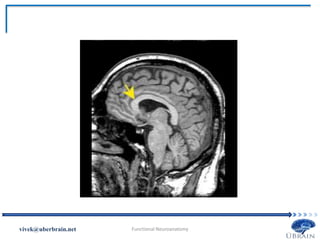

Vivek Misra

fornix